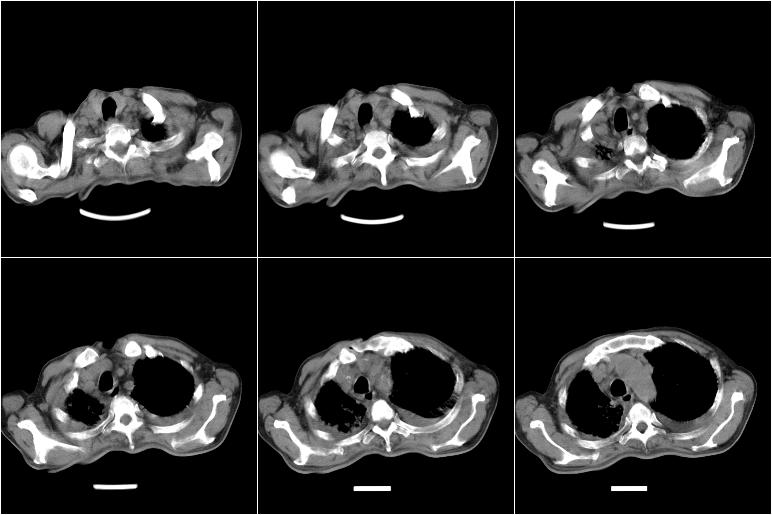

以下是引用边生丽在2009-8-17 11:43:00的发言:[br][br] [br] 右肺中心型癌伴右肺下叶不张、双肺转移并癌性淋巴管炎、心包和双侧胸腔积淮(转移?)、脑转移、肝转移、多骨(颅骨、椎骨)转移。 [br] [br]

以下是引用随光逐影在2009-8-17 14:09:00的发言:[br]支持 右肺中央型癌伴右肺下叶肺不张,纵隔淋巴结转移,双肺转移并癌性淋巴管炎,心包和双侧胸腔积液,脑转移、肝转移、多发性骨(颅骨、脊椎)转移。